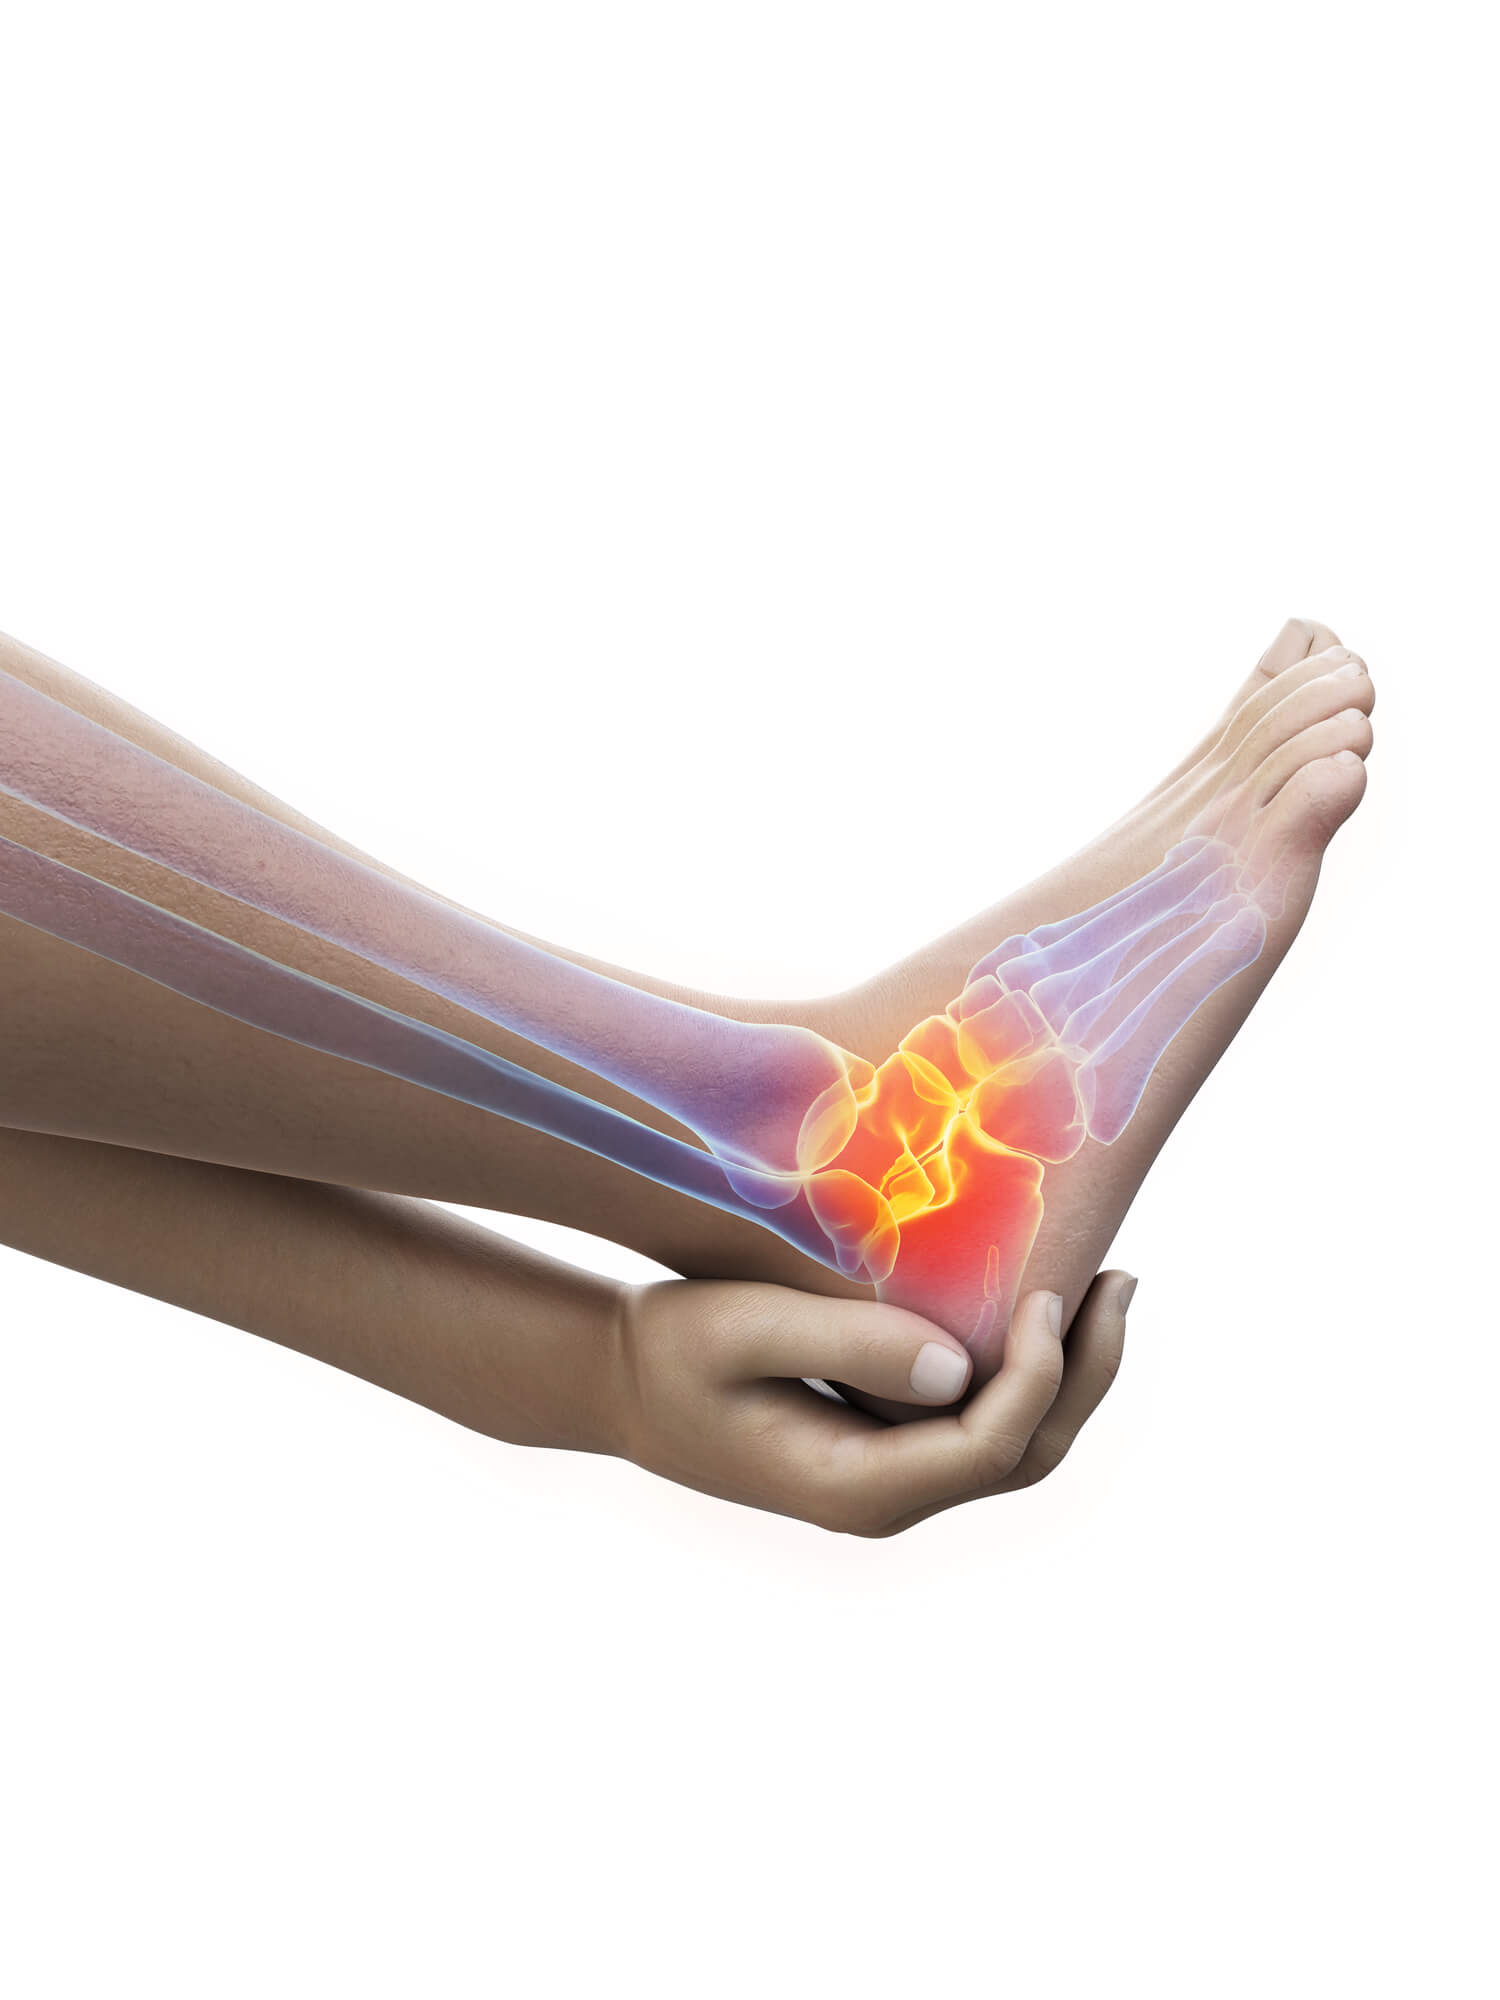

Sprained Ankle: What’s the Treatment?

A sprained ankle occurs when the ligaments that support the ankle are stretched or torn. This can happen if you fall, twist your ankle, or wear high heels for too long.

Treatment for a sprained ankle usually involves rest, ice, compression, and elevation (R.I.C.E.).

You may also need to wear a splint or brace and take pain medication.

In some cases, a sprained ankle can lead to chronic (long-term) pain, swelling, and muscle weakness. This is known as chronic ankle instability (CAI). CAI occurs when the ligaments in the ankle are repeatedly stretched or torn.

People with CAI often have cankles because of the constant swelling in the ankle.

Your doctor will likely ask you about your medical history and symptoms. He or she will also physically examine your foot and ankle, looking for signs of swelling, redness, and tenderness. In some cases, your doctor may order one or more imaging tests to help confirm the diagnosis. These tests may include:

Your doctor will likely recommend conservative treatment measures first. These may include:

Resting your foot and ankle. Restrictions for activities that put stress on your foot and ankle, such as running or playing tennis.

Icing your foot and ankle. Apply ice for 20 minutes several times a day to help reduce swelling.

Wearing supportive shoes. Choose shoes with a low heel and good arch support.

If a conservative approach doesn’t relieve your symptoms, your doctor may recommend more aggressive treatments. These may include:

Physical therapy. Physical therapists can teach you exercises to help stretch and strengthen your Achilles tendon and other foot and ankle muscles.

Surgery. In some cases, surgery is necessary to repair the damaged Achilles tendon or remove excess tissue around your ankle.

If you have an Achilles tendon injury, it’s important to seek medical attention as soon as possible. These injuries require prompt treatment to minimize the risk of long-term complications. Early diagnosis and treatment can also help speed up the rehabilitation process.

After the initial period of rest, your doctor may recommend a physical therapy program to help you regain strength and flexibility in your Achilles tendon. Physical therapy may involve a combination of exercises, stretching, and massage. Your therapist will also likely recommend that you use equipment such as ankle weights or an Achilles tendon support strap to help with the healing process.

If you have an Achilles tendon injury, it’s important to follow your doctor’s instructions for treatment. If you don’t, you may be at risk for further injury or even a complete tear of the tendon.